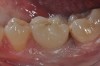

Fig 1. Clinical view of the maxillary right first premolar implant in a healthy 63-year-old woman. The swelling in the tissue surrounding the first premolar implant bled on probing and was associated with peri-implant mucositis. The lesion developed 4 years after implant placement.

Figure 1